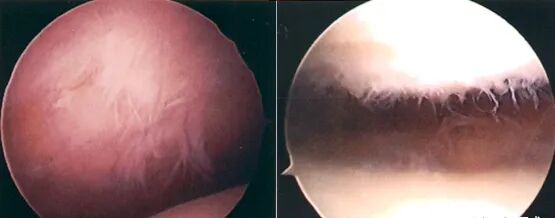

病理分级

关节镜下可将髌骨软化分为5级:

Ⅰ级:关节软骨失去珍珠样外观而变得较暗淡,局部软化,肿胀区或纤毛化区的直径<0.5cm。

Ⅱ级:关节软骨软化区内出现毛刷状或纤毛化改变,深达1~2mm,直径≤1.3cm。

Ⅲ级:软骨的毛刷状或纤毛化改变达关节软骨厚度一半以上,直径>1.3cm,关节软骨表面类似蟹肉样改变,表面有多发软骨碎片附着其下的软骨。

Ⅳ级:关节软骨全层受侵,软骨下骨暴露,表现为进展期髌股关节炎。

Ⅰ~Ⅱ级为早期,主要保守治疗。

Ⅲ~Ⅳ级为进展期,需手术及关节镜治疗。

• 关节镜:是髌骨软化症确诊与治疗的有效手段之一,可以在镜下直接观察软骨面的变化,但不能够观察到软骨下骨的变化